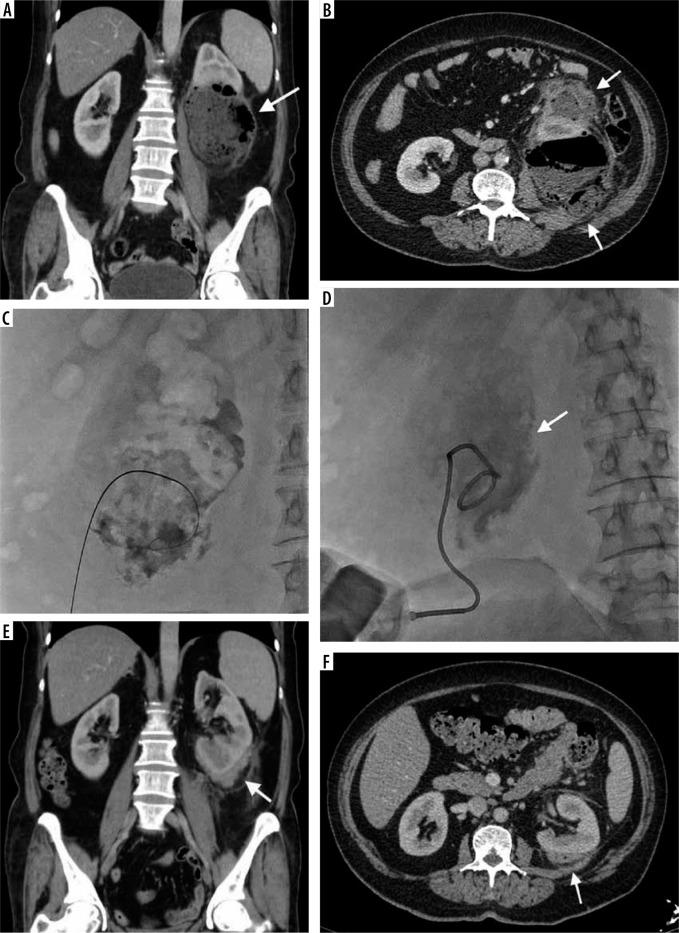

经皮导管引流术治疗腹膜后脓肿:单中心8年经验

Percutaneous catheter drainage in retroperitoneal abscesses: a single centre's 8-year experience.

We have investigated the technical and clinical success of percutaneous catheter drainage (PCD) in retroperitoneal abscesses and factors that may affect the outcome.

The study cohort included 45 patients (17 females and 29 males, with mean age of 56.3 years) that were treated between 2012 and 2020. Forty-seven abscesses were managed with PCD under ultrasonography, computed tomography, or fluoroscopy guidance. Patients' demographics, lesion locations, predisposing factors, clini-cal presentation, etiology, radiological findings, technical factors, and outcome parameters were presented using exploratory and descriptive statistics.

Abscesses were located in the psoas ( = 25, 55.3%), renal-perirenal ( = 7, 14.8%), and pararenal ( = 14, 29.7%) compartments. The mean preprocedural volume was 263.3 (30-1310) ml. Pain (abdominal and back) (57.4%) and fever (17%) were the most frequent presenting symptoms. The most common predisposing factors were previous surgery ( = 17, 36.1%) and diabetes mellitus ( = 11, 25.5%). Clinical success was attained in 89.3% of abscesses (definitive treatment 72.3% and partial success 17.0%). There was a statistically significant difference between the iatrogenic and non-iatrogenic groups regarding clinical success ( = 0.031). No mortality was encountered. The complication rate was 6.6% and were all minor. The average rate of recurrence was 10.6%. The mean time to catheter removal was 15.8 ± 13.2 days.

PCD is a safe and effective procedure in the treatment of retroperitoneal abscesses. Procedure-related mortality, morbidity, and complication rates are low. Underlying etiology is a significant factor affecting the outcome. Nevertheless, PCD may provide definitive treatment in the majority of patients.